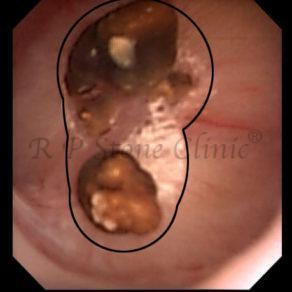

The Below Images Show Small Stones attached to the Renal Papillae.